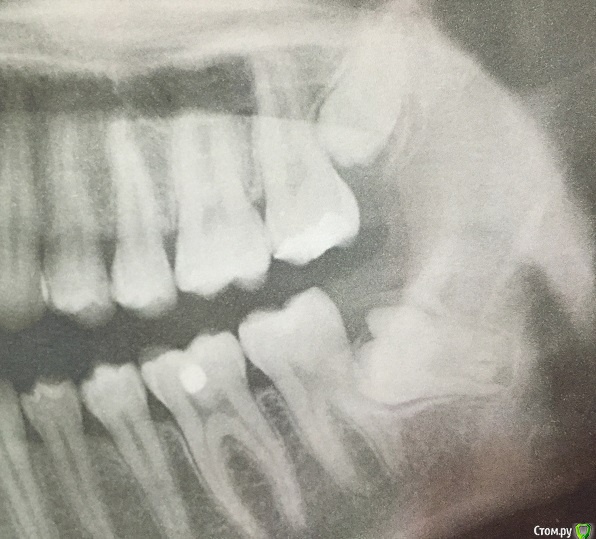

Craysley@rambler.ru Опубликовано 27 июня, 2016 Поделиться Опубликовано 27 июня, 2016 (изменено) Здравствуйте!Полгода назад переодически начали возникать неприятные ощущения в области нижних жевательных зубов с левой стороны во время жевания твердой пищи. Оказалось, растет зуб мудрости. Соседние зубы сейчас стали более чувствительными. Левой стороной теперь практически не жую, болит. А так, больше никаких неудобств кроме боли при жевании нет. Врач советует, прежде чем удалять восьмерку, подождать еще месяц-другой, может боль пройдет. Восьмерка еще не прорезалась. Посоветуйте удалять ли сейчас или есть смысл ждать? P.S.: А что за белое пятнышко на шестерке снизу? (зуб пломбирован) Изменено 27 июня, 2016 пользователем Craysley@rambler.ru Ссылка на комментарий

red_butler Опубликовано 28 июня, 2016 Поделиться Опубликовано 28 июня, 2016 Удалять4.6 зуб перелечивать 2 Ссылка на комментарий

St. Опубликовано 28 июня, 2016 Поделиться Опубликовано 28 июня, 2016 Он, как мне кажется, растет нормально. Нет, он тоже растет в соседний зуб, только не настолько наклонен как левый.Удаляйте все зубы мудрости. 1 Ссылка на комментарий